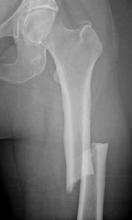

Courtesy of Dr. Joseph Lane/Journal of Bone and Mineral Research

This AP radiograph of the left femur demonstrates a substantially transverse femoral fracture and associated diffuse periosteal new bone formation and focal cortical thickening, consistent with atypical femoral shaft fracture.